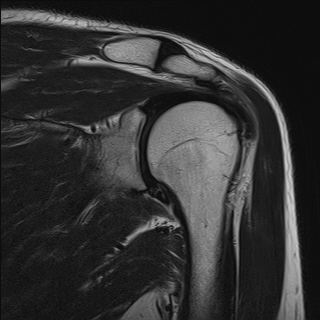

ÀÌ È¯ÀÚ¿¡¼­ º¸ÀÌ´Â °ß°©°ñÀÌ»ó¿îµ¿ÁõÀº ÆÈÀ» ¿Ã¸° ÈÄ ³»¸± ¶§¸¸ ¹ß»ýÇϴµ¥ Àü°Å±ÙÀÇ Áö±¸·Â ¾àÈ­³ª ´ÉÇü±ÙÀÇ

¾àÈ­¸¦ ¿øÀÎÀ¸·Î ÃßÁ¤ÇÒ ¼ö Àִµ¥ ±ÙÀüµµ°Ë»ç¿¡¼­´Â ½Å°æº´Áõ ¼Ò°ßÀ» È®ÀÎÇÒ ¼ö ¾ø¾ú´Ù.

ÃÊÀ½ÆÄ°Ë»ç¿Í ÀÚ±â°ø¸í°Ë»ç¿¡¼­ Ãæµ¹ÁõÈıº ¼Ò°ßÀ» º¸À̹ǷΠ°ß°©°ñÀÌ»ó¿îµ¿ÁõÀÌ È¸Àü±Ù°³

ÆÄ¿­ÀÇ ¿øÀÎÀ¸·Î ÆÇ´ÜÇϱâ´Â ¾î·Æ°í ¼­·Î °ü·Ã ¾øÀÌ Á¸ÀçÇÏ´Â °ÍÀ¸·Î ÆÇ´ÜµÈ´Ù.